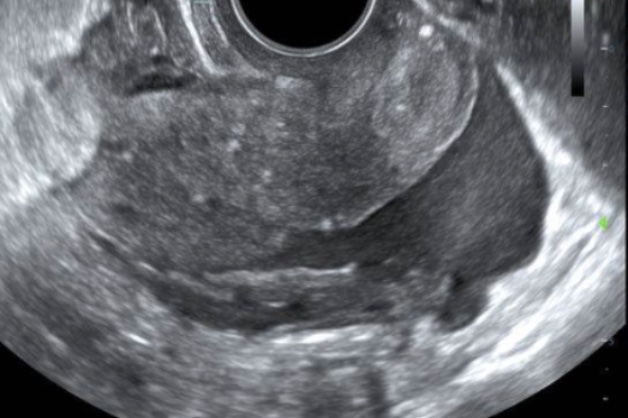

Bedside point of care ultrasound is performed and reveals the following images (shown below). What’s the diagnosis? Scroll down for answer.

Transvaginal US

Answer: Ruptured Cornual (ie Interstitial) Ectopic Pregnancy

For example, our patient had what LOOKED to be a gestational sac in the uterus, but it was actually a pseudogestational sac (see mid uterus view above). Upon further investigation, we found the complex adnexal mass in addition to the intrauterine ‘sac’.